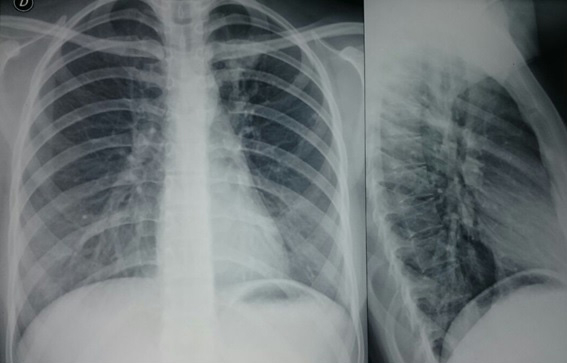

Los gases arteriales, electrolitos séricos, electroforesis de proteínas, pruebas de coagulación, cuantificación de inmunoglobulinas séricas, los estudios de valoración renal (parcial de orina y sedimento urinario, creatinina, nitrógeno ureico) y hepática (bilirrubinas, alanino transaminasa, aspartato transaminasa, fosfatasa alcalina, albúmina sérica, tiempo de protrombina) resultaron normales. El Elisa para VIH dio negativo. Los Anticuerpos antinucleares y Anti-DNA bicateriano resultaron negativos. El Derivado Proteíco Purificado (PPD) fue de 7 mm a las 72 horas de lectura. Los estudios imagenológicos informaron en la radiografía de tórax y el apicograma un área de aumento de la densidad de localización apical izquierda con ocupación intersticial en relación a proceso consolidativo (Fig. 1).